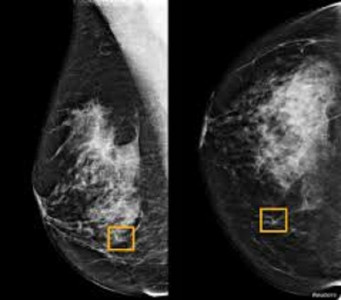

Study finds Google system could improve breast cancer detection

The findings of the study, developed with Alphabet Inc’s DeepMind AI unit